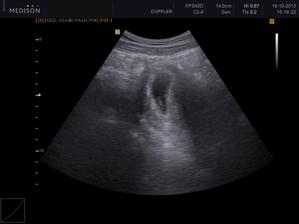

52DC/3 (2013/10/16) 7+3tt .... 1. utzv ..... srdeční akci! Jupíííí, prý vše Ok. Další KO za tři týdny (6/10).